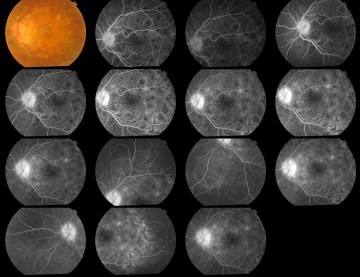

Image